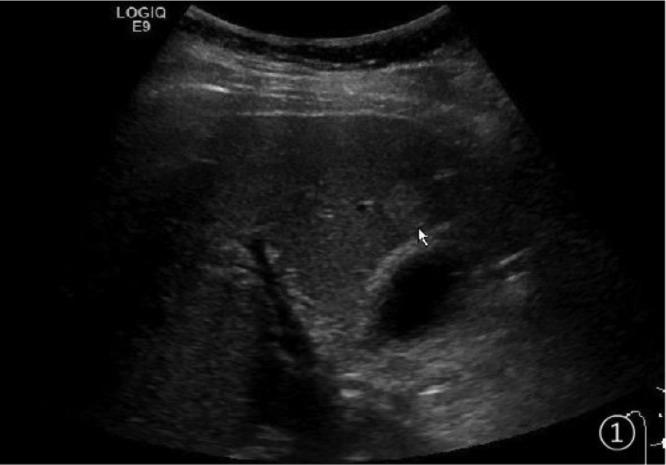

多模态超声诊断甲状腺髓样癌肝转移1例报告

A case report of diagnosis of liver metastasis of medullary thyroid carcinoma by multimodal ultrasound.

Medullary thyroid carcinoma is a rare malignant neuroendocrine tumor. Distant metastasis is difficult to detect early. It is most common in lung, liver, bone and brain. This case was reported as liver metastasis of medullary thyroid carcinoma in an elderly woman, but routine ultrasound findings were atypical. After a series of relevant imaging examinations, contrast-enhanced ultrasound and ultrasound-guided puncture biopsy were used to confirm the nature of the intrahepatic lesions. Therefore, we believe that multimodal ultrasound is of great value in the diagnosis of liver metastasis of medullary thyroid carcinoma.

摘要

甲状腺髓样癌是一种罕见的恶性神经内分泌肿瘤。远处转移很难早期发现。最常见于肺、肝、骨和脑。本文报道了一例老年女性甲状腺髓样癌肝转移病例,但常规超声表现不典型。经过一系列相关影像学检查后,采用超声造影及超声引导下穿刺活检来明确肝内病变的性质。因此,我们认为多模态超声在甲状腺髓样癌肝转移的诊断中具有重要价值。